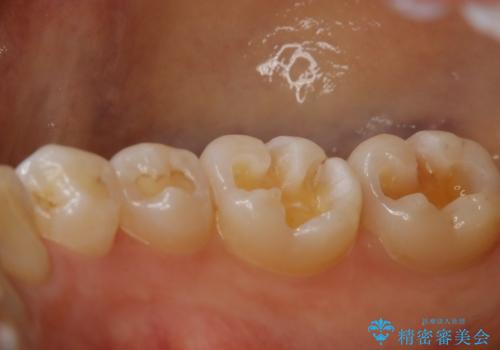

奥歯を綺麗にしたい

- 右下6・7番の咬合面に詰められた保険材料が劣化していたので、審美性・切削量を考慮しセラミックインレー治療を選択しました。

劣化した保険材料・虫歯を全て除去した上で形成しています。